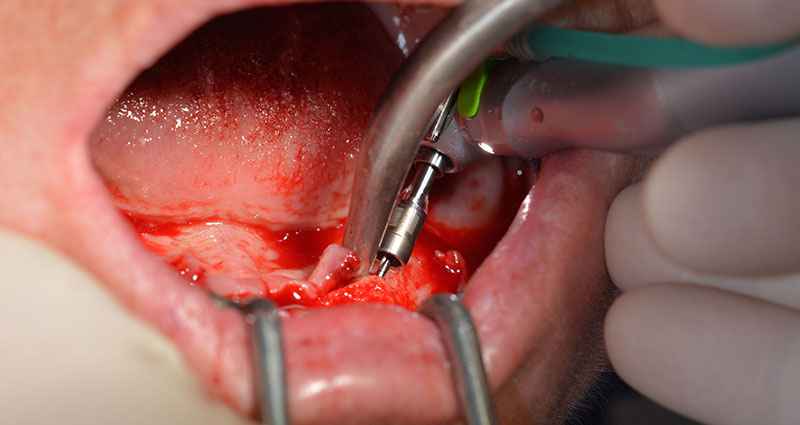

Dies entspricht der nächsten Position der Voreinstellung am Implantmed. Zu erkennen ist die etwa 45-Grad-Schräghaltung des W&H Winkelstückes nach mesiokaudal in Regio 45, um den Nervus mentalis zu schonen. Das Foramen mentale gilt als anatomische Orientierung für alle Bohrungen in diesem Bereich. Die anschließenden Bohrungen werden mit einer reduzierten Umdrehungszahl von 300/min durchgeführt (Abb. 10 und 11).